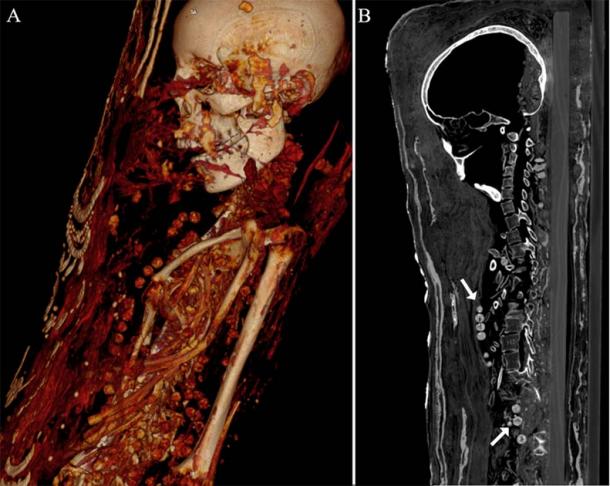

Both females were buried with beautiful necklaces. CT scan showed the beads from the woman’s necklace around the neck and body. (Zesch S, et al. PLOS One / CC BY 4.0)

The girl died between the ages of 17 and 19 and had stood at about 156 cm (5.1 in.) tall when alive. Her stucco-shrouded portrait mummy is housed at the Museum of Egyptian Antiquities, Cairo, and it shows her wearing several necklaces, which were all identified by the scans. The girl had a “vertebral hemangioma,” a benign tumor in her spine, which the researchers say is normally found in older adults. While her brain “had shrunk over the millennia” it was still preserved, but neither the man’s or woman’s brains have survived the test of time.

Top image: Left: Female portrait mummy scanned thanks to modern CT technology. Center and right: Scan of female mummy. The female was placed on a wooden board, wrapped in a textile and decorated with 3D plaster, gold and a whole-body portrait. Source: (Zesch S, et al. / PLOS One)